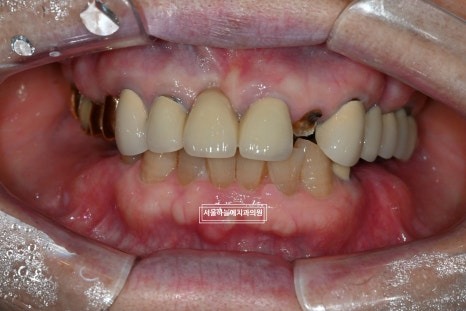

처음 내원 시 상태

처음 내원 당시 엑스레이와 구강 상태를 보면

앞니는 파절되어 있었고

아래 어금니가 없는 기간이 길어

위 치아와 잇몸이 맞닿을 정도로 공간이 부족,

아래 앞니 역시 심하게 마모된 상태였습니다.